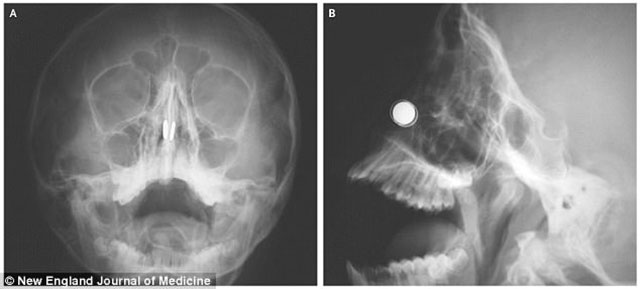

Kıbrıs’ta yaşayan 11 yaşındaki çocuk burnu kanarken acı içinde acile geldi. Röntgen filmlerine bakan doktorlar burun direğinin yanlarında birbiriyle aynı hizada diske benzer iki yabancı madde buldu.

11 yaşındaki çocuk burnuna mıknatısları sokunca mıknatıslar içerde birleşmiş, bu yüzden kendi başına çıkarmayı başaramamıştı.

Mıknatıslar durdukça kıkırdağı aşındırmaya başlamıştı. Acil bir müdahaleyle mıknatısları çıkarmaya çalışan doktorlar da ilk denemede başarısız olduktan sonra burnun iki yanına başka mıknatıslar yerleştirerek çıkarmayı başardı.